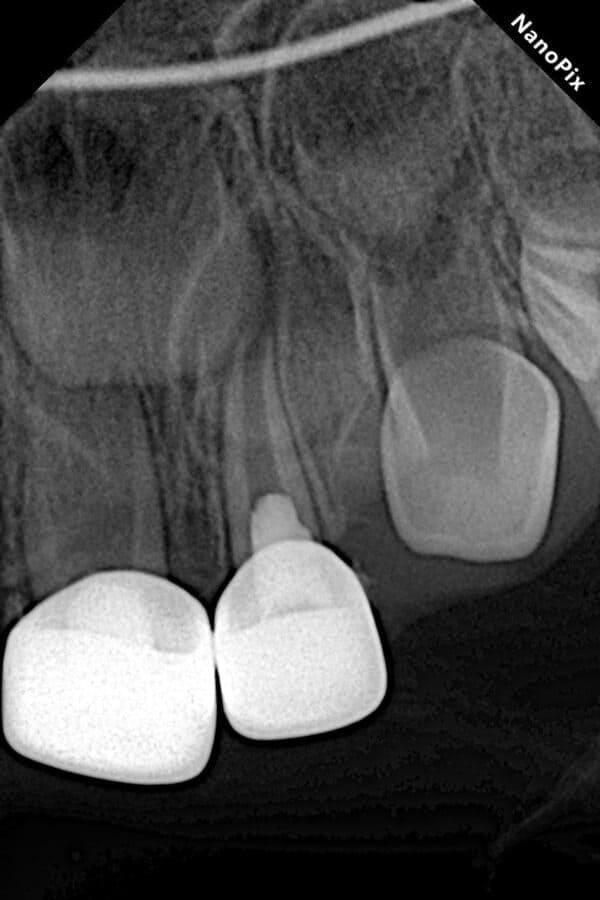

Поява перших постійних зубів, а це шості зуби, відбуваються, коли дитина ще не може, як слід провести їх гігієну та попіклуватись про їх здоров’я. Тому, на жаль вони і вражаються карієсом досить швидко. Пацієнт ще маленький – 6 років, а лікування потребує дорослого: зі знеболенням та ізоляцією. Саме таке і було проведене в даному випадку: зуб очищений від інфікованих тканин, відновлений фотополімерним матеріалом і готовий довго служити юному господарю.